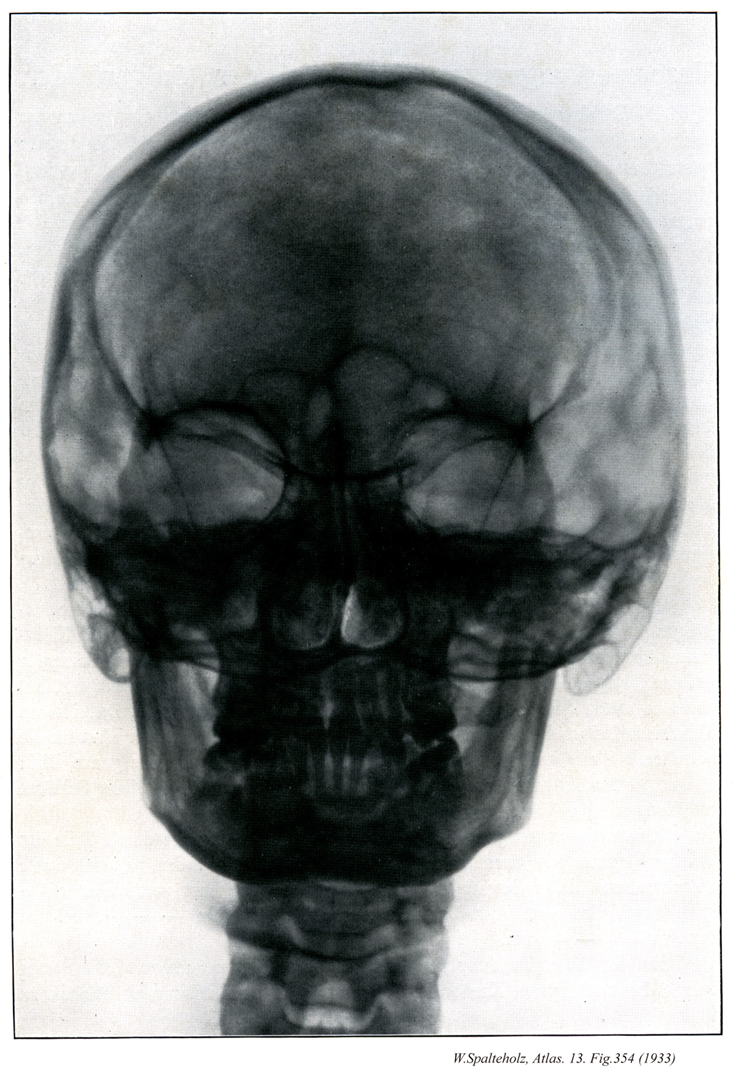

354

- 354_00【Bones of cranium; Skull bones頭蓋骨;ズガイコツ Ossa cranii】

→(頭蓋は15種23個の骨、すなわち10種16個の頭蓋骨および5種7個の顔面骨とにより形成されている。頭蓋骨は中枢神経系および感覚器に接する部分を形成する骨格で後頭骨(1個)、蝶形骨(1個)、側頭骨(1対2個)、頭頂骨(1対2個)、前頭骨(1個)、篩骨(1個)、下鼻甲介(1対2個)、涙骨(1対2個)、鼻骨(1対2個)、及び鋤骨(1個)である。頭蓋を構成する骨の分類には諸学者による見解の相違があり、後頭骨、蝶形骨、側頭骨、頭頂骨、前頭骨の5種7個を脳頭蓋とし、他の10種16個を顔面骨とする意見もある。)